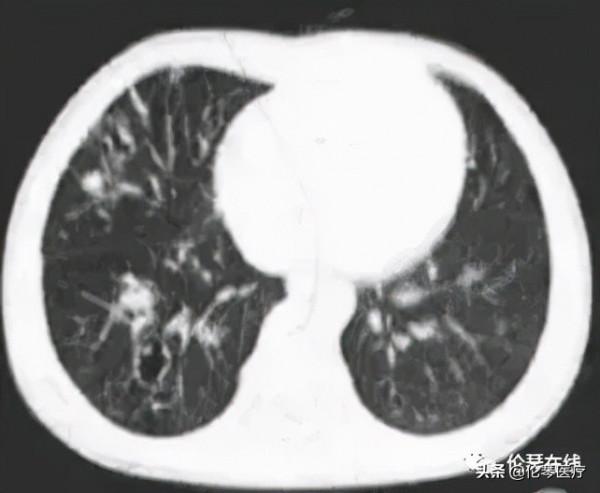

右肺多發囊狀、穴窟樣低密度影和小片狀滲出

多發空洞,呈“隧道徵”

雙肺斑片狀滲出,並可見小囊狀影